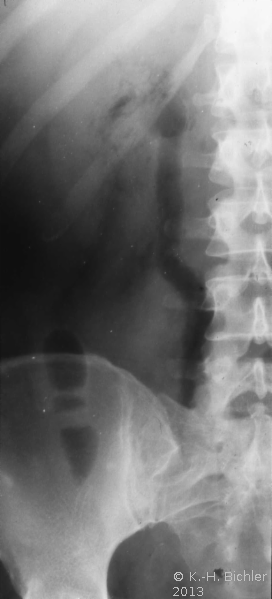

Akute nekrotisierende E. coli-Infektion. Dabei kommt es durch die Glukose spaltenden Bakterien zur Gasentwicklung im Nierenparenchym. Bei den Patienten liegt häufig ein Diabetes vor

Literatur:Schainuck, L. I. et al: "Emphysematous Pyelonephritis", Amer J Urol, 44, 134-139, 1968. Diese Form der Pyelonephritis kommt auch im Kindes- und Jugendalter vor. Das Krankheitsbild ist gekennzeichnet von Bauchschmerzen und Fieber. Die Erkrankung tritt akut mit Zeichen der Allgemeininfektion auf. Im Ausscheidungsurogramm findet sich eine Gasfüllung der ableitenden Harnwege (Abbildung 14).

Die Infektion verläuft destruktiv und prognostisch ungünstig. Bei Nichtansprechen der Therapie ist die Nephrektomie unverzichtbar.